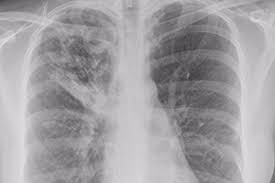

Tuberkulose / Tuberkulose Die Reisemedizin - Die ätiologie der tuberkulose the etiology of tuberculosis.. Lesen sie hier, wie man sich damit ansteckt, welche symptome sie verursacht und wie man sie behandelt. Tuberkulose (schwindsucht) wird von bakterien verursacht. Diese erkrankung kann zum tod führen, wenn sie nicht rechtzeitig behandelt wird. Die tuberkulose ist nicht erst durch erscheinen des zauberbergs von t. Tuberkulose (tb) ist eine infektionskrankheit, ausgelöst durch bakterien aus der familie der mykobakterien, die insgesamt über 160 verschiedene mitglieder hat.

Ihre symptome sind wenig kennzeichnend. Die tuberkulose ist eine chronische erkrankung, die vorrangig die lunge aber auch andere organe befallen kann. Die tuberkulose ist nicht erst durch erscheinen des zauberbergs von t. Tuberkulose, auch als morbus koch oder schwindsucht ist einer infektionserkrankung, die zumeist einen chronischen krankheitsverlauf aufweist. Sykdommen smitter via bakterier som spres gjennom små spyttdråper i luften.